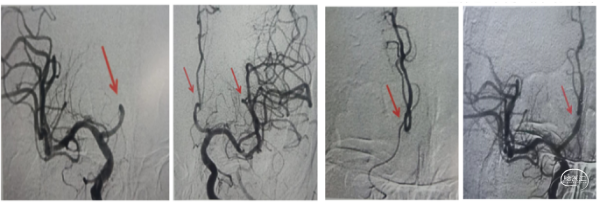

右侧颈总造影发现,右侧颈内动脉起始处有斑块,两处充盈缺损。

使用泥鳅导丝试探,很幸运,毫不费劲就通过了狭窄处,因此考虑此处未完全闭塞,而且远处的栓子可能就来源于此处。将5F125cm Navien沿着泥鳅导丝轻松通过狭窄处,进行抽吸清理颈内动脉可能滞留血栓。跟进8F导引导管通过狭窄部位起到支撑作用。

上干和大脑前为功能区血管,应该开通:

先开通大脑中M2段。支架导管到位,确认远端通畅,尼科医疗的Reco支架3X20mm到位,5F Navien跟到M1,一边抽吸一边拉栓,一把拉通。

注意:应该微导管半收拢支架钳夹血栓,缓慢回拉,防止牵拉血管支撑组织导致脑出血。

再开通大脑前A2段,同样尼科医疗的Reco支架3X20mm到位,5F Navien 跟进A1,半收拢支架,一边抽吸一边拉栓,一把拉通。

回头处理颈内动脉起始部。常规保护伞4-6mm保护下行4-6mm球囊扩张,并自膨支架7-9-40mm植入。